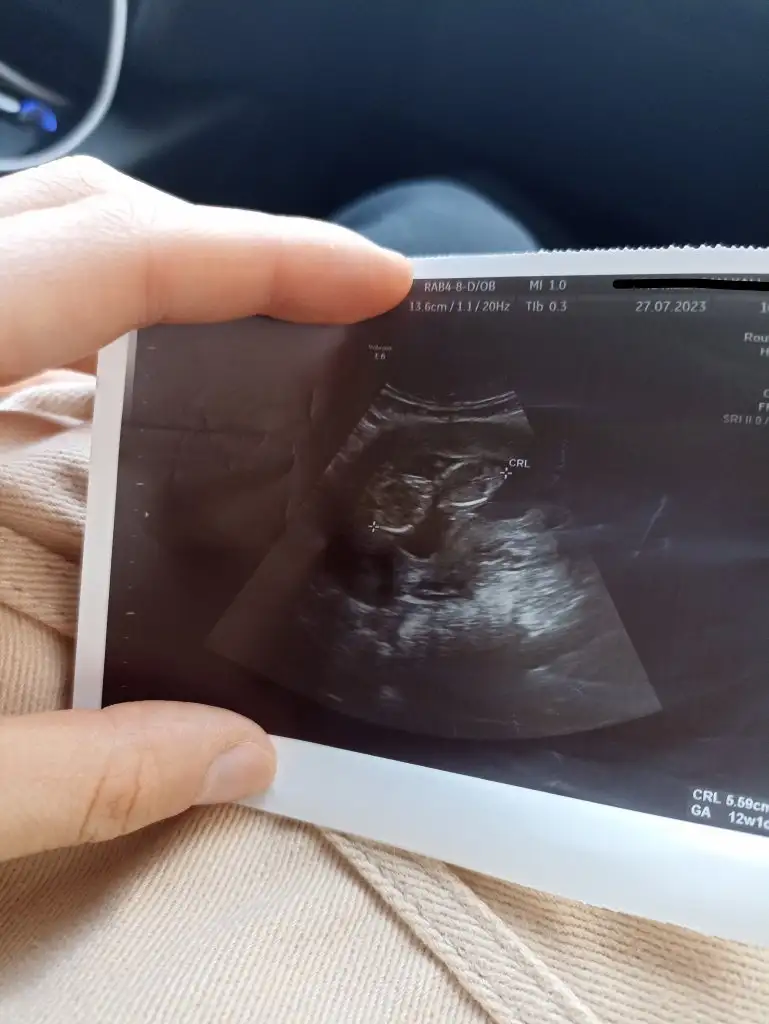

bana da yorum yapın lütfen 12+4

N Nakafile merhaba. Benim 12. haftada sırtı dönük mu anlayamadigim bir ultrason kağıdım var bu haftayı hevesle bekledim cocugum çok belirsiz bakayım siz cinsiyeti hakkinda ne diyeceksiniz acaba rica etsem yorumlar misniz :')